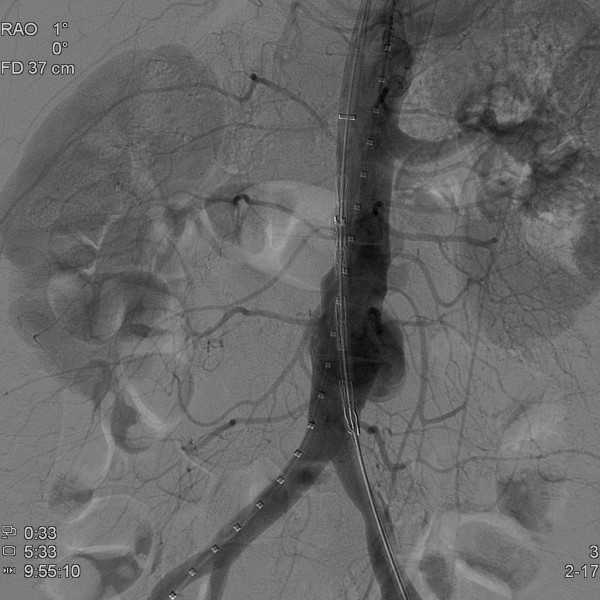

오산한국병원에서는 지난 5월 28일 오전, 제 3영상의학과 지주연 과장의 시술로 복부대동맥류 환자에 대한 스텐트 삽입술을 성공적으로 완료하였습니다.

복부대동맥류는 뱃속의 시한폭탄이라 일컬어지며 병원에 도착하기전에 사망하는 비율이 50%를 넘어가고, 살아 있어도 증상과 파열이 있는 경우에는 수술을 하더라도 성공률이 50%를 넘지 못하고 있는 실정으로 응급수술을 요하는 매우 위험한 질환입니다.

전국적으로 시술가능한 병원이 몇군데 안될 정도로 어려운 질환임에도 불구하고 이번에 복부대동맥류 스텐트 삽입술을 본 병원에서 성공하게 됨으로써 오산 및 인근지역내에 타의 추종을 불허하는 질높은 수준에 의료서비스를 제공할 수 있는 종합병원임을 다시한번 입증하게 되었습니다.